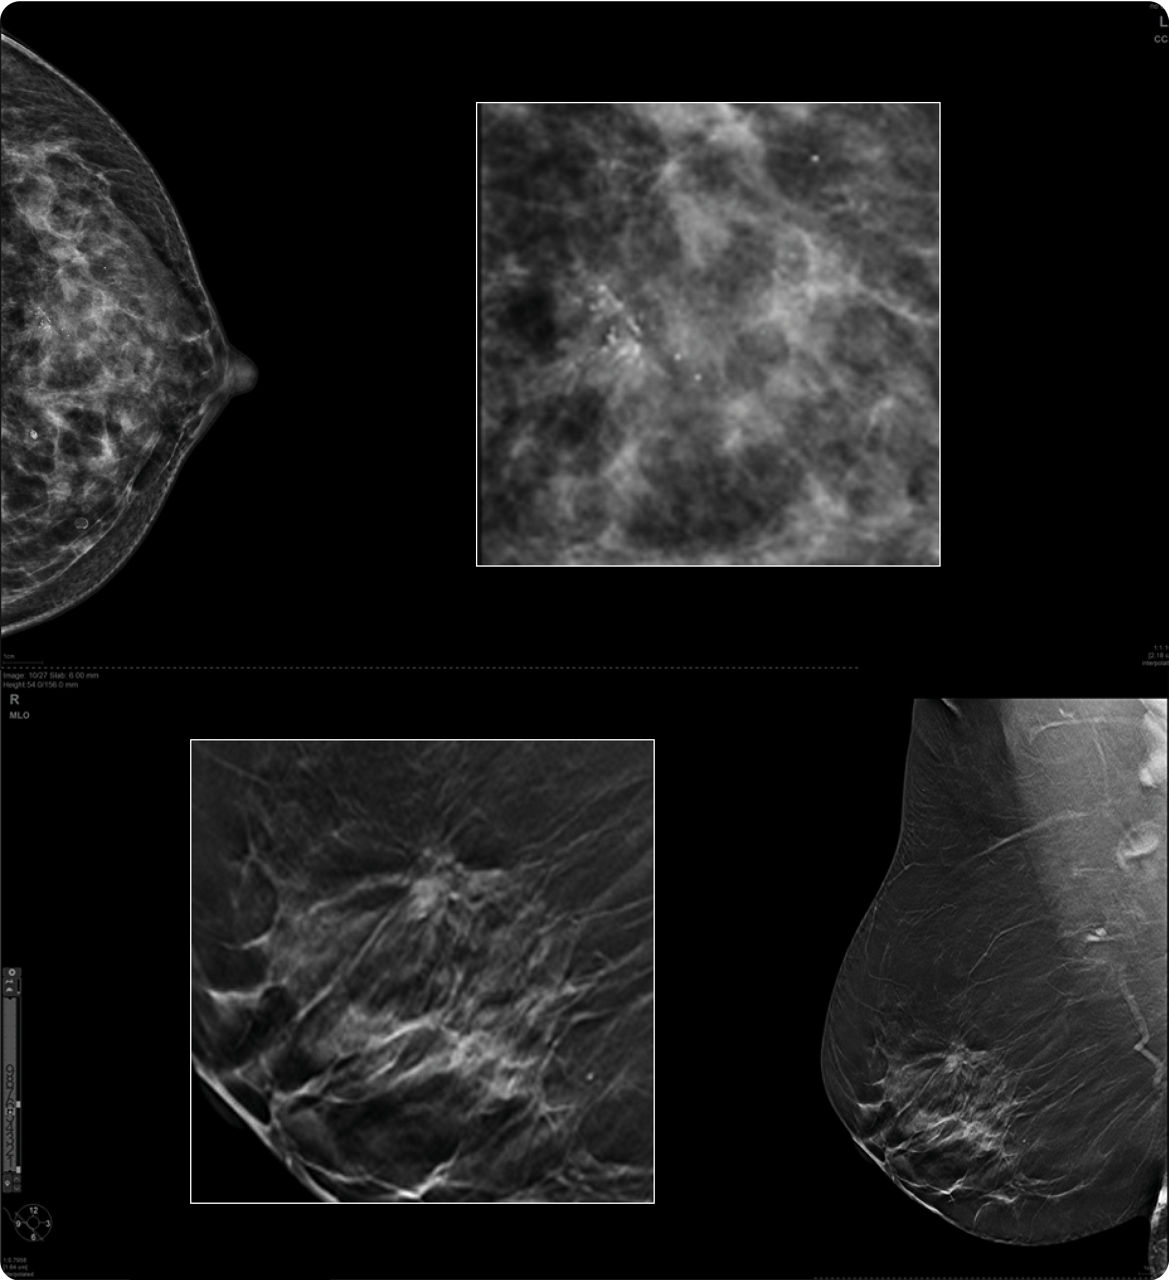

SUPPORTS CLEAR ANSWERS

Your partner for clinical confidence

Confidence starts with clarity. Pristina Duo delivers exceptional image quality, which can improve accuracy1 and help limit recalls8—enabling earlier, decisive cancer detection.

• The Senographe Pristina Platform utilizes 3D + 2D acquisitions significantly increases the cancer detection rate compared to 2D alone by up to 90%, with no increase in recall rate.9

• The Pristina Platform delivers superior diagnostic accuracy compared to 2D alone for all breast densities, including dense breasts.1

• 3D technology on the Senographe Pristina Platform proven to reduce patient recall rate vs. 2D alone.8